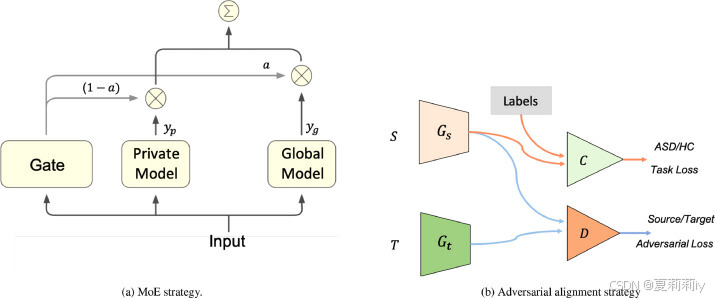

(1)Mixture of experts (MoE) domain adaptation

①Experts: mean deep learning models

②MoE: trainable gating network used in feed-forward neural network

③Domain adaptation strategies with FL:

④The final output of their network:

where the is the gating function in MoE and they use an non-linear layer

to represent it,

is Sigmoid,

and

are learnable weights

(2)Adversarial domain alignment

①They trained a local feature extractor for the source site

②They also trained a local feature generator for the target site

③They align distribution of and

by training a adversarial domain discriminator

④ and

aim to confuse

by adding noise (generate

and

,

denotes noise generator) and

aims to identify the domain

⑤To discriminate domain:

⑥第二步中的损失??第二步是什么?不变但

更新?以前也没这个东西啊怎么能叫更新?

⑦Algorithm(在这个第八行感觉出⑤和⑥俩损失就是直接都用上就行,但是作者也没有特别的解释,不知道从哪扒来的):